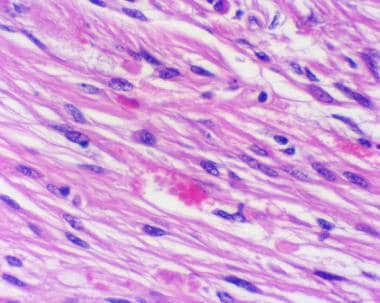

多形性黄色星形细胞瘤的特征是细长的梭形细胞,胞质嗜酸性,偶尔有巨细胞,其中一些可能表现为泡沫状或黄色改变(见下图)。嗜酸性颗粒体,一种病因未知的退化性细胞现象,也可能在毛细胞星形细胞瘤中遇到,几乎总是存在。 这些肿瘤中的大多数还表现出细胞周网状蛋白,这一特征较初被认为是诊断性的,但后来发现不太可靠。网状蛋白对应于与每个肿瘤细胞相关的基底膜。淋巴细胞和浆细胞浸润也是常见的发现。

多形性黄色星形细胞瘤的特征是大的多核细胞,胞质呈泡沫状,通常混有一群较小的纤维细胞。肿瘤细胞的细胞边界通常独特。(苏木精和曙红,20倍原始放大倍数。)

单核炎性细胞浸润对于多形性黄色星形细胞瘤并不少见。(苏木精和曙红,40×原始放大倍数。)